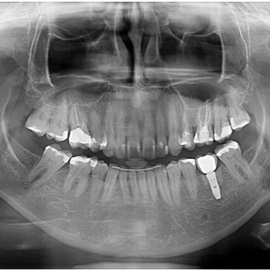

Pacjentka po ekstrakcji kilku zębów, z implantacją natychmiastową, odroczoną. Zdjęcie pantomograficzne wykonano pięć lat po implantacji. Widoczna stabilna sytuacja kostna i dziąsłowa.